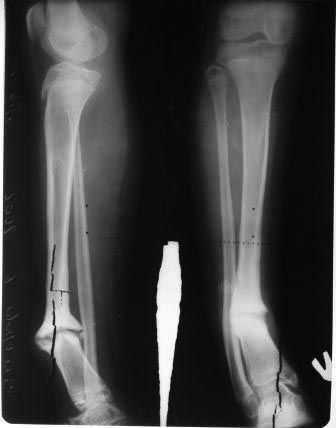

Коллеги, обратилась пациентка 12 лет, со слов матери 5 лет назад заболела острым гематогенным остеомиелитом, 4 раза оперирована в обл. детской больнице, после образовался ложный сустав, в центре произведена костная аутопластика, нагноение, после отторжения аутокости рана зажила и рецидив псевдоартроза 2 года назад(все это со слов матери). Клинически тугой ложный сустав н/з голени, деформация,укорочение 2см, девочка ходит самостоятельно, прихрамывает. Пока определенного мнения нет, повторно открывать не хочется, какие будут мнения по поводу БИОС- после остеотомии м/б кости и аппаратной коррекции деформации или сначала профилактически спейсер с антибиотиком ? и продолжать ЧКДО? Прилагается Р-граммы, обещают принести и предыдущих Р-грамм.( пациентка из другой обл.) С уважением Абдурашид.

Ув. Абдурашид, зачем выполнять БИОС ребенку 12 лет с активно функционирующими зонами роста?! В этой ситуации можно справиться с помощью ЧКДО. Ложный сустав гипертрофический. Достаточно будет выполнить остеотомию малоберцовой кости и остеотомию большеберцовой кости через зону ложного сустава с формированием несвободного костно-надкостнично-мышечного лоскута (см. схему) с последующей коррекцией деформаций АВФ. Выполнение вмешательства спустя не менее 1 года после перенесенного воспалительного процесса. Позже постараюсь выложить Р-граммы результатов лечения подобных больных.

При тугом ложном суставе прекрасно срастется при закрытой коррекции оси и длины большеберцовой кости дистракцией, ее не надо остеотомировать, достаточно малоберцовую.